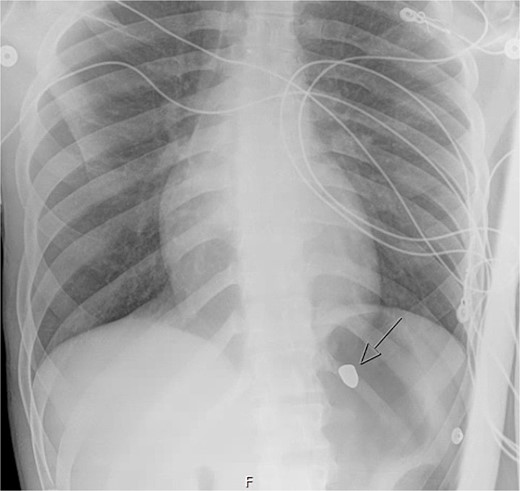

A repeat otolaryngology endoscopy exam on HD 2 revealed a 1.5 cm wound in the posterior pharyngeal wall, confirming the suspicion that the bullet entered the posterior of the mouth, was swallowed, and was now migrating down the GI tract. Serial X-rays tracked its transit (Fig. 4). Despite treatment, his condition remained critical. He underwent tracheostomy, gastrostomy, and diaphragmatic pacemaker placement. The patient was discharged to a long-term care facility on HD 22 but succumbed to complications from AIDS and pneumonia months later.